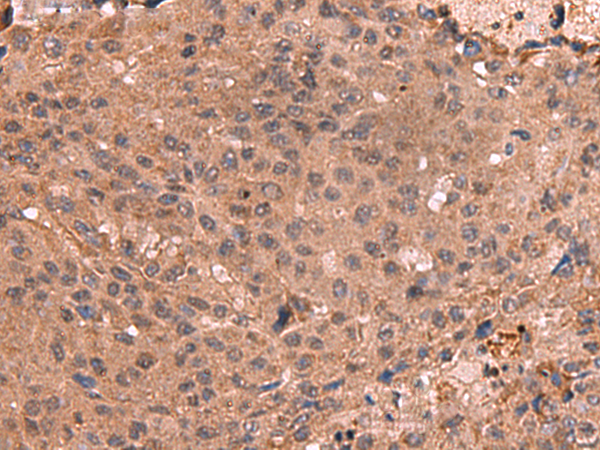

The image is immunohistochemistry of paraffin-embedded Human colorectal cancer tissue using 47669(IST1 Antibody) at dilution 1/40.(Original magnification: 200)